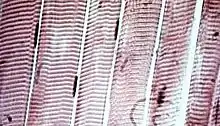

![]() The body contains three types of muscle tissue: (a) skeletal muscle, (b) smooth muscle, and (c) cardiac muscle. (Same magnification) | |

Muscle tissue varies with function and location in the body. In vertebrates the three types are: skeletal or striated; smooth muscle (non-striated) muscle; and cardiac muscle.[1] Skeletal muscle tissue consists of elongated, multinucleate muscle cells called muscle fibers, and is responsible for movements of the body. Other tissues in skeletal muscle include tendons and perimysium. Smooth and cardiac muscle contract involuntarily, without conscious intervention. These muscle types may be activated both through the interaction of the central nervous system as well as by receiving innervation from peripheral plexus or endocrine (hormonal) activation. Striated or skeletal muscle only contracts voluntarily, upon the influence of the central nervous system. Reflexes are a form of non-conscious activation of skeletal muscles, but nonetheless arise through activation of the central nervous system, albeit not engaging cortical structures until after the contraction has occurred.

There are three types of muscle tissue in vertebrates: skeletal, cardiac, and smooth. Skeletal and cardiac muscle are types of striated muscle tissue.[1] Smooth muscle is non-striated.

Vertebrate skeletal muscle tissue is an elongated striated muscle tissue with the fibres ranging in width from three to eight micrometers and in length from 18 to 200 micrometers. In the uterine wall during pregnancy they enlarge in length from 70 to 500 micrometers.[3] Skeletal striated muscle tissue is arranged in regular, parallel bundles of myofibrils containing the many contractile units known as sarcomeres, which give the tissue its striated (striped) appearance. Skeletal muscle, is voluntary muscle anchored by tendons or sometimes by aponeuroses to bones, and is used to effect skeletal movement such as locomotion and to maintain posture. Postural control is generally maintained as an unconscious reflex, but the muscles responsible can also react to conscious control. An average adult man is made up of 42% of skeletal muscle as a percentage of body mass, and an average adult woman is made up of 36%.[4]